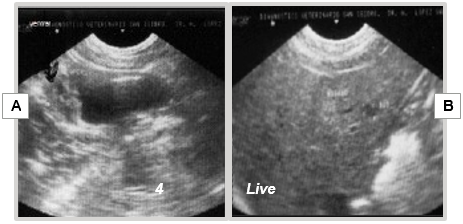

The postoperative period progresses without particular issues, except for slight hematuria lasting 24-48 hours. The patient demonstrates a favorable course of bladder healing (Figure 18A) and early signs of hepatic metastasis at 4 months (Figure 18B).

Figure 18 Ultrasonographic image at 4 months post-cryosurgery.

A) Scar on the dorsal wall of the bladder; B) Hepatic metastasis.

Evolution: The patient's progress occurs without significant clinical signs, except for mild hematuria. Symptomatic and ultrasonographic follow-up at 4, 6 months, and 1 year shows no recurrences (Figures 24) (Figure 25).

Figure 24 Ultrasonographic follow-up at 4 months post-cryosurgery.

Figure 25 Ultrasonographic follow-up at 6 and 12 months post-cryosurgery.